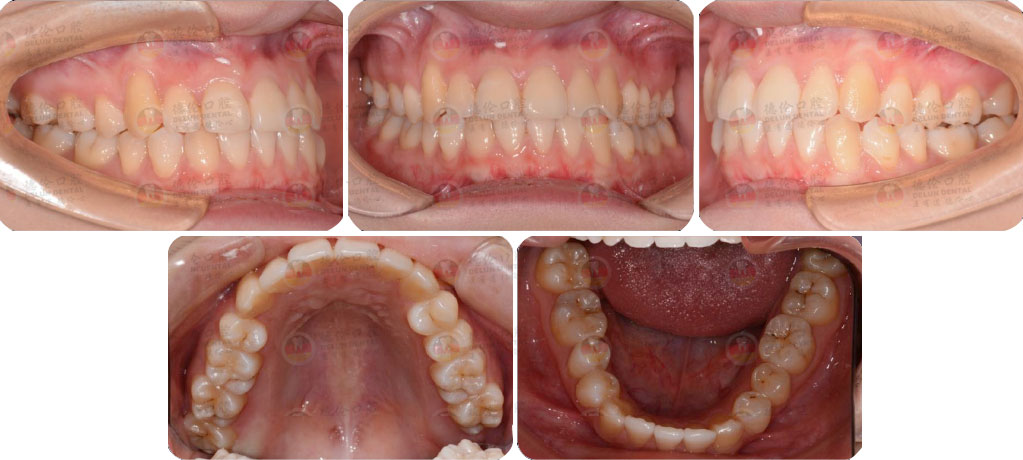

德倫口腔矯正診室指定專家團是以德倫口腔總院正畸科主任、時代天使全國智美隱形矯治病例大賽三等獎得主――熊小琴主任,和德倫口腔總院正畸科資深專家、隱形矯正培訓講師、有 26 年口腔醫療臨床經驗的王蘇靜醫生,共同領銜的 16 位隱形正畸認證醫師。指定專家團實力雄厚,臨床經驗豐富,內含多名口腔正畸專業博士、碩士組成的正畸博碩專家團和第 18 屆雅加達亞運會中國代表團時代天使口腔保障營專家團。